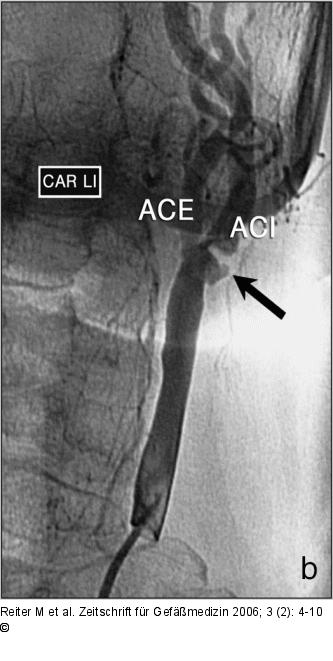

Abbildung 4a-b: Arteria carotis interna (a) MR-Angiographie der Karotiden. Bds. findet sich eine Stenose der A. carotis interna: rechts eine Fadenstenose, links eine ~70%-Stenose mit verifiziertem Ulkus. (b) zeigt die korrespondierende i. a. DSA-Aufnahme der linken Seite; (Z) zeigt die ACI-Stenose. |

(a) MR-Angiographie der Karotiden. Bds. findet sich eine Stenose der A. carotis interna: rechts eine Fadenstenose, links eine ~70%-Stenose mit verifiziertem Ulkus. (b) zeigt die korrespondierende i. a. DSA-Aufnahme der linken Seite; (Z) zeigt die ACI-Stenose. |